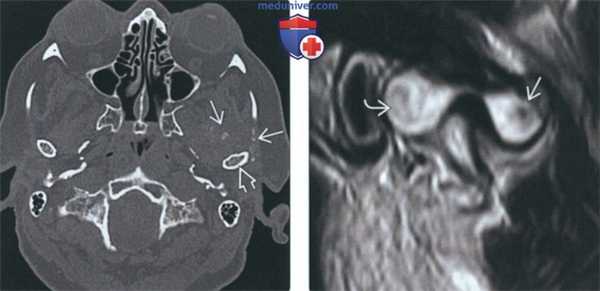

(Слева) При аксиальной КТ в костном окне в правом височно-нижнечелюстном суставе (ВНЧС) визуализируются множественные мелкие кальцинированные узелки. Мыщелок склерозирован, слегка деформирован, суставное пространство сужено в передних отделах из-за дегенеративных изменений.

(Слева) При MPT T2FS в кососагиттальной проекции определяется растяжение капсулы правого височно-нижнечелюаного сустава с наличием обызвеавленных свободных тел с низкой интенсивностью сигнала, окруженных жидкостью с гиперинтенсивным сигналом.

(Справа) При МРТ Т1ВИ FS с КУ в сагиттальной проекции в передних отделах ВНЧС визуализируется кистозное образование, накапливающее контраст по периферии в виде «ободка». Верхнее суставное пространство расширено. Периферический «ободок» представляет собой синовиальную оболочку, накапливающую контраст.

(Слева) На аксиальной КТ в костном окне у пациента с синовиальным хондроматозом левого ВНЧС спереди и снаружи от мыщелка определяется объемное образование с множественными точечными обызвествлениями.

(Справа) На косой сагиттальной MPT(Т2 ВИ) определяется неоднородный сигнал позади мыщелка, сопоставимый с хрящевыми узлами, и обызвествление/оссификация спереди от него.